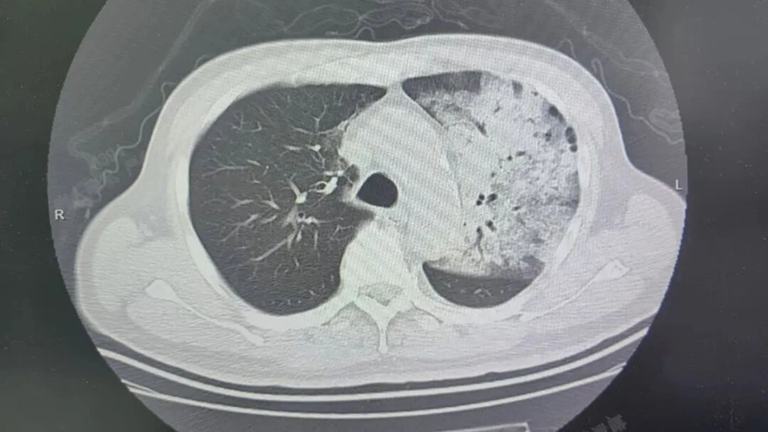

Sau khoảng một tuần điều trị tại bệnh viện địa phương, bệnh tình của ông đột ngột xấu đi. Bệnh nhân bắt đầu khó thở, rối loạn ý thức. K ết quả chụp CT cho thấy 2 phổi bị nhiễm trùng nặng, gần như “trắng xóa” . Dù đã được hỗ trợ thở máy nhưng tình trạng oxy máu vẫn không cải thiện.

Nhờ can thiệp bằng ECMO, các bác sĩ mới tạm thời ổn định được dấu hiệu sinh tồn cho bệnh nhân.